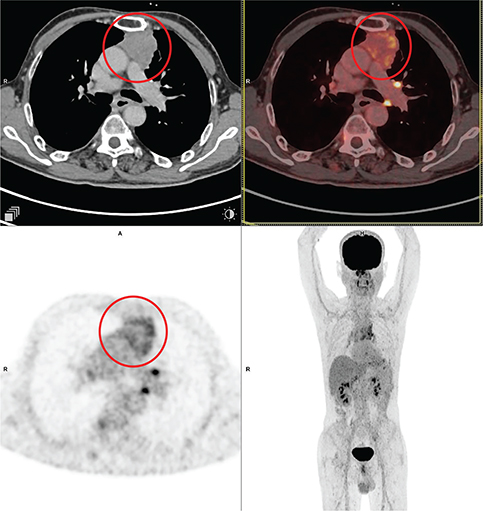

Aggressive thymic epithelial tumors frequently invade or extrinsically compress the superior vena cava (SVC), causing SVC syndrome. Thymic carcinomas typically exhibit more irregular contours, heterogeneity related to hemorrhage, necrosis, and cystic change, as well as higher levels of local vascular and mediastinal invasion and lymphadenopathy (3032). An example of thymic carcinoma is shown in Figure 2.

Fig 2

Figure 2. Thymic carcinoma. Anterior mediastinal mass that was pathologically confirmed as thymic carcinoma. FDG PET/CT images include axial CT (top left panel), fused axial PET/CT (top right panel), axial PET (bottom left panel), and maximum intensity projection (MIP) PET image (bottom right panel). In the red circle, there is a soft tissue density mass with irregular nodular contour showing heterogenous enhancement in CT with heterogenous FDG uptake on PET. There is loss of intervening fat plane with the body of sternum anteriorly and the pulmonary trunk posteriorly concerning for infiltration. There was additional mild to moderately FDG-avid regional lymph nodes and pleural deposits (not on the included PET/CT images and could be appreciated on the MIP image) that were suggestive of metastatic disease.